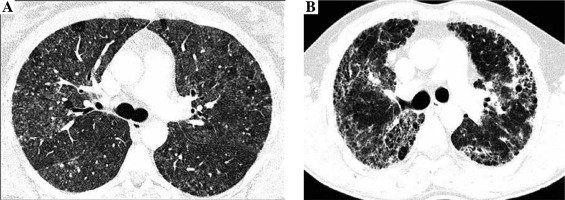

Radiologists evaluated the presence and intensity of typical HP features in CT images, including centrilobular nodules, diffuse ground glass opacifications, air trapping, and mosaic attenuation, and features of lung fibrosis, such as reticulation, traction bronchiectasis, and honeycombing. Lung fibrosis on CT images was staged as: 0. No fibrosis (Fig. 1A), 1. Areas of reticulation with traction bronchiectasis, 2. Advanced lung fibrosis with honeycombing and bronchocentric fibrosis (Fig. 1B). Characteristics of study population is presented in Table 1.

Fig. 1

Non-fibrosing and fibrosing hypersensitivity pneumonitis. Figures present CT axial images of the lung window. A) Bilateral patchy ground-glass opacities, diffuse, poorly defined centrilobular nodules, focal regions of decreased attenuation corresponding to air trapping lobules and normal lungs, characteristic for HP mosaic attenuation, and no features of lung fibrosis (stage 0). B) Fibrosing hypersensitivity pneumonitis – patchy ground-glass opacities and diffuse reticulation with traction bronchiectasis and focal honeycombing, which are the features of advanced lung fibrosis (stage 2)